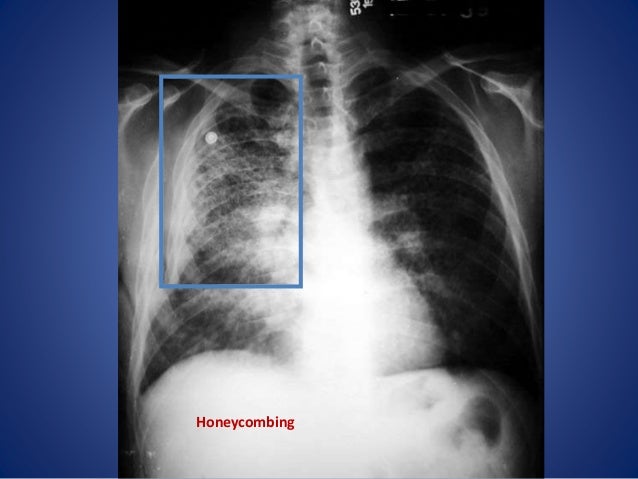

Chest x. ray interpretation and teaching from image.slidesharecdn.com Abnormalities such as cancerous tumors usually appear brighter because they are denser. Breast cancer and some benign breast conditions are denser than fat and appear a lighter shade of gray or white on a mammogram. This is called a triple assessment. The earliest sign of breast cancer can be an abnormality depicted on a mammogram, before it can be felt by the woman or her physician. It looks for early changes that could be a sign of cancer. The photographs included on this page are the results of reconstructive procedures performed by the surgeons at the center for restorative breast surgery. Your skin may turn pink, red, tanned, or look like it has sunburn. Contrast studies might need more preparation, and could cause some side effects and discomfort, depending on the type.

Chest X-Ray for the Diagnosis of Lung Cancer from www.verywellhealth.com American cancer society, 9 oct 2017. The bone at the site of the cancer may look ragged instead of solid. When breast cancer spreads to other parts of the body, it is called metastasized breast cancer.breast cancer and its complications can affect nearly every part of the body. A 3d mammogram is used to look for breast cancer in people who have no signs or symptoms. That indicates that the lesion likely contains a variety of elements, which may or may not indicate breast cancer. It can also be used to investigate the cause of breast problems, such as a breast mass, pain and nipple. The earliest sign of breast cancer can be an abnormality depicted on a mammogram, before it can be felt by the woman or her physician. Fat and muscle absorb less, so they show up in different shades of gray.